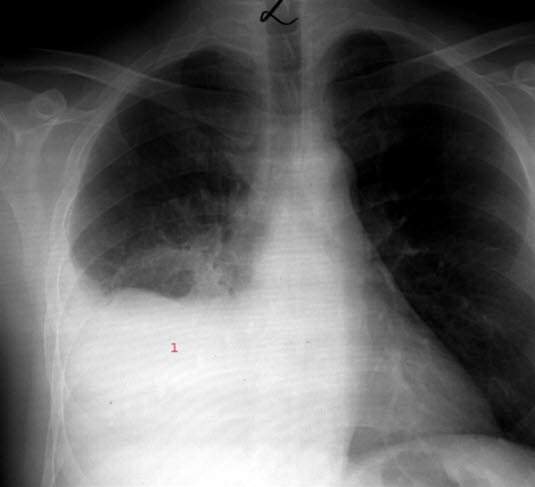

Lungebetennelse i nedre del av høyre lungeTypisk sykehistorie og funn ved legeundersøkelsen er noen ganger nok til at legen blir sikker på diagnosen. Blodprøver som høy CRP, høy senkning eller økt antall hvite blodlegemer styrker mistanken om lungebetennelse. Sikkert bevis for at det foreligger lungebetennelse, får man fra et røntgenbilde eller ultralydundersøkelse av lungene.